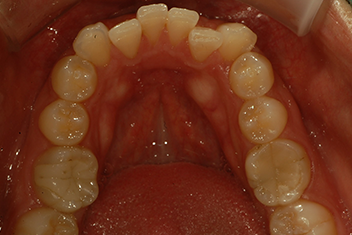

앞니 돌출 해소 케이스2

치료 기간12개월

경미한 앞니 돌출을 투명교정으로 빠르게 개선